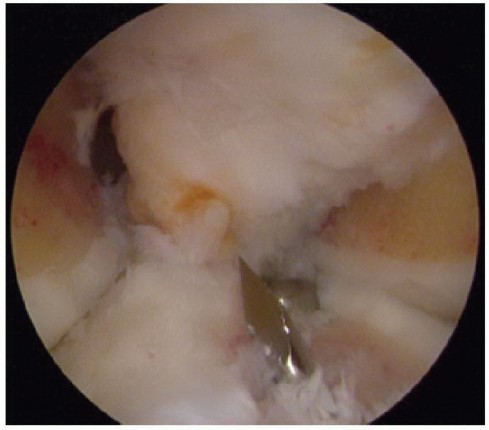

Before delivery of the graft into the recipient site, place the 10-inch needles from the passage sutures through the miniarthrotomy and posterolateral capsule to assist in delivery of the graft (

TECH FIG 3A

). Posterolateral exposure, retraction, and needle retrieval are identical to an inside-out repair technique. This suture will assist in the delivery and reduction of the meniscus under the femoral condyle.

Alternatively, a Nitinol wire loop can be delivered “outsidein” through the posterolateral exposure into the joint. The Nitinol wire is arthroscopically retrieved with a grasper through the anterior arthrotomy. Place the passage sutures through the Nitinol loop and deliver them through the posterolateral capsule.

Attempt to deliver the passage suture needles through the capsule relative to their position in the

meniscus (

TECH FIG 3B

). Use the popliteus tendon and the popliteal hiatus in the graft as a guide for suture placement.

TECH FIG 3 • Delivery of lateral meniscus. A. Teninch needles from the passage suture are placed through the posterolateral capsule and retrieved by the assistant. B. Inside-out vertical sutures are placed through the appropriate location within the posterolateral capsule. C. The dovetail graft is delivered into the recipient site.

(continued)

By simultaneously inserting the shape-matched donor graft into the tibial recipient site and pulling on the previously placed passage suture, the graft is delivered to reestablish the normal insertion site (

TECH FIG 3C

).

A varus stress to the knee, combined with pulling on the posterior passage sutures, will help reduce the posterior horn under the femoral condyle.

Matching the anterior cortices (graft and recipient) and bringing the knee through a range of motion will assist in final AP positioning. Visualizing the meniscus' position arthroscopically will confirm proper seating of the graft (

TECH FIG 3D,E

Place additional inside-out meniscal sutures with the suture cannula placed in the anteromedial portal. The scope is placed into the miniarthrotomy (

TECH FIG 3F,G

Additional anterior sutures can be placed through the anterior arthrotomy using standard open suturing techniques.

Tie the sutures with the knee in flexion (lateral transplants).

An interference screw or transosseous suture fixation may be placed with the slot technique, but this is typically unnecessary with the dovetail and keyhole techniques.

TECH FIG 3 •

D. Lateral meniscus bone bridge delivered into the tibial trough. E. Meniscus reduced under condyle. F. Placing inside-out sutures. G. Final meniscus transplant. 3. ## Medial Meniscus Graft Preparation